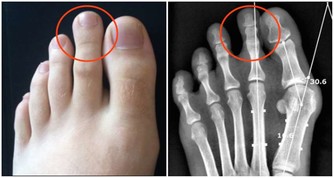

2、影響視力

開燈睡覺會成倍增加患近視的幾率!

因為會影響孩子的眼部網狀激活系統,易造成視網膜的損害,對孩子的視力發育不利。

根據對479名2-16歲的近視患者研究,睡在燈光下的兩歲以下的嬰兒與睡在黑暗中的嬰兒相比,

近視發病率要高出四倍!燈光越強,幾率越高。